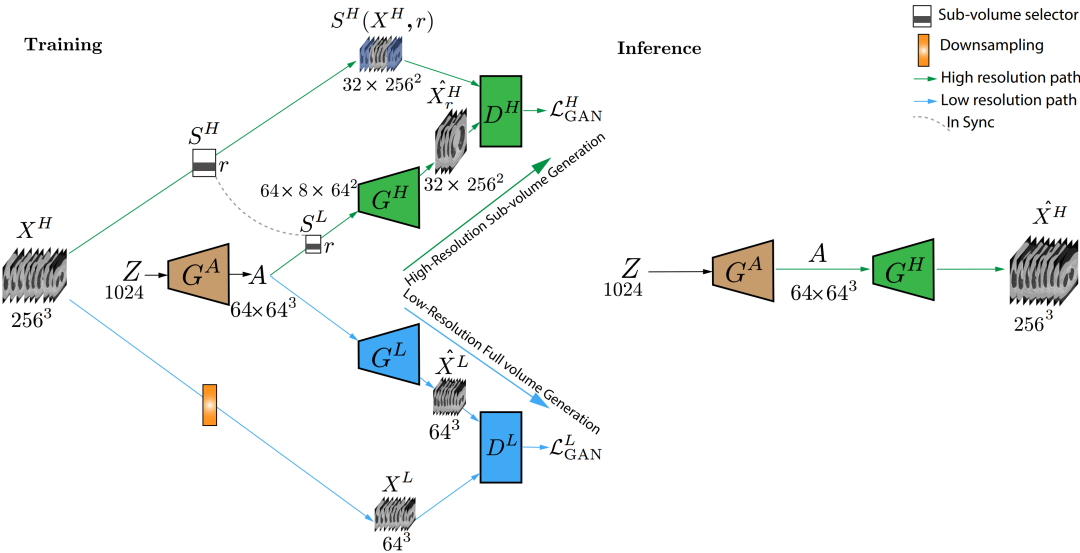

4 三维生成GAN

医学图像数据本质上是三维的,前面介绍的一些工作大多是二维切片图像的仿真,这里我们再介绍一些三维仿真GAN的工作,相比于二维图片生成计算复杂度更高,因此一些新的工作致力于在生成高分辨率图片的同时,设计更加高效的生成架构。

[8] Jin D, Xu Z, Tang Y, et al. CT-realistic lung nodule simulation from 3D conditional generative adversarial networks for robust lung segmentation[C]//International Conference on Medical Image Computing and Computer-Assisted Intervention. Springer, Cham, 2018: 732-740.

[9] Sun L, Chen J, Xu Y, et al. Hierarchical Amortized GAN for 3D High Resolution Medical Image Synthesis[J]. IEEE journal of biomedical and health informatics, 2022, 26(8): 3966-3975.